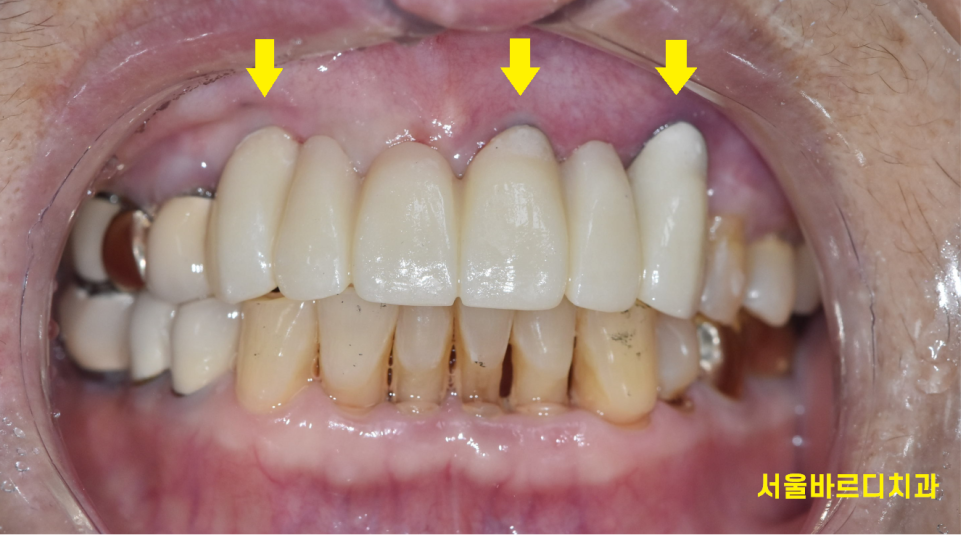

아래 앞니는 자연치아이고

위에 치아 6개를 보철하신 상태네요~

송곳니부터 송곳니까지요.